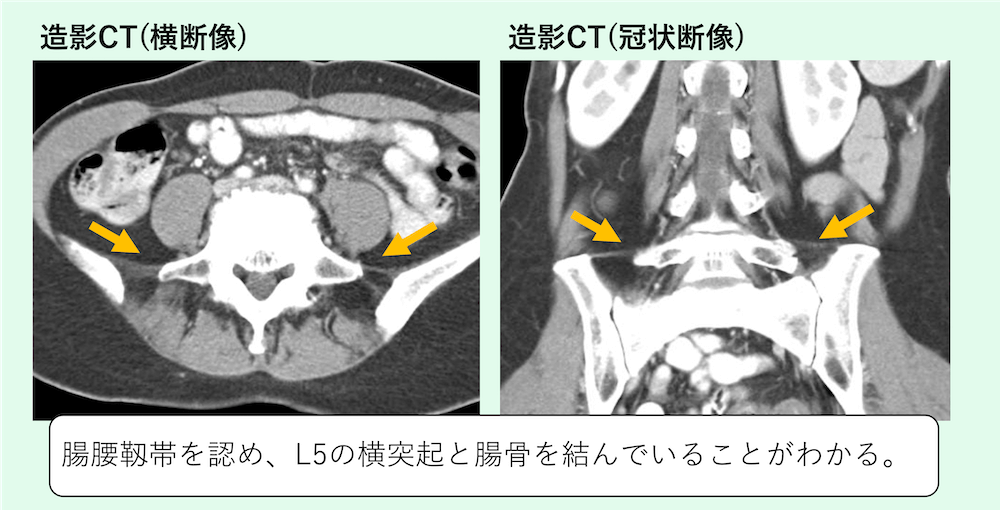

腸腰靱帯を認め、L5の横突起と腸骨を結んでいることがわかります。

左右の高さはやや異なりますが両側で、腸腰靱帯を認め、L5の横突起と腸骨を結んでいることがわかります。